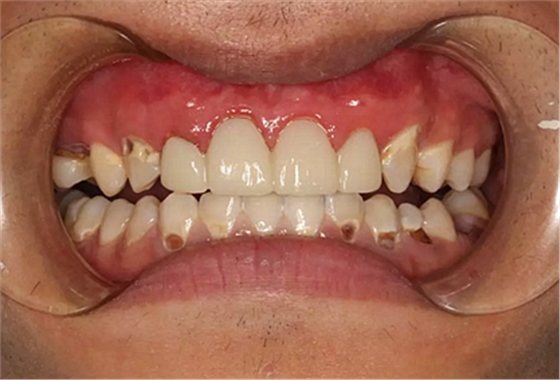

我們的主人今年才25歲,可卻從很小的時候就嗜好喝可樂等碳酸飲料,幾年下來,讓我們兄弟姐妹們整天浸在碳酸里受這蝕骨之痛,原本皎潔的外貌如今早己經(jīng)是腐蝕不堪、丑陋無比,更有甚者,一些兄弟姐妹們已經(jīng)病入膏肓,被病痛折磨奄奄一息。

下面是醫(yī)生眼中和ct下的我們

一身病痛啊

牙結石、牙齦炎癥、牙體殘缺、慢性牙髓炎、蛀牙......

才二八芳華的我們

已經(jīng)滿目蒼夷